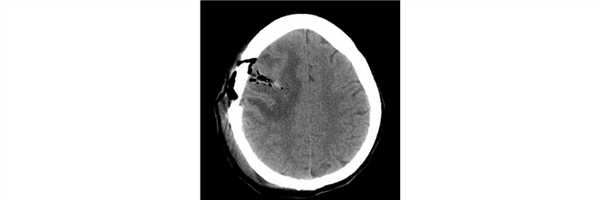

Пациент 38 лет дважды оперирован по месту жительства по поводу опухоли правой теменно-затылочной области, выполнена резекционная трепанация черепа (гистологический диагноз - SEGA - субэпендимарная гигантоклеточная астроцитома). Вторая операция осложнилась развитием раневой ликвореи и менингита. Дефект черепа не закрыт. Адъювантная терапия не проводилась. При контрольной МРТ картина рецидива опухоли с крупным кистозным и солидным компонентом.

Проведена операция - микрохирургическое удаление опухоли правой теменно-затылочной области с использованием нейрофизиологического мониторинга

Послеоперационный период протекал без осложнений. При контрольной СКТ картина радикального удаления опухоли.

Гистологический диагноз - морфологическая картина, иммунофенотип и данные молекулярно-генетического исследования в большей степени соответствуют анапластической плеоморфной ксантоастроцитоме, WHO Grade III, BRAF-мутантной. Рекомендуется предоставить препараты от первых операций.

В препаратах от предыдущих операций идентичная преимущественно веретеноклеточная опухоль с участками выраженного полиморфизма ядер и клеток. Проведено сравнение препаратов предыдущих операций с препаратами от настоящего вмешательства - картина опухолей идентична и соответствует анапластической плеоморфной ксантоастроцитоме.

Пациент после выписки направлен на проведение адъювантной терапии (в т.ч. тартегтной терапии).